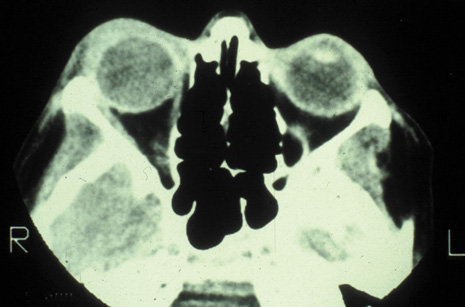

Rhinocerebral mucormycosis originates as a rhinitis, parapharyngitis, or sinusitis, and spreads by invasion of blood vessel walls, causing a necrotizing vasculitis with thrombosis of the vascular lumina and resultant infarction. The patient typically presents with unilateral orbital apex syndrome, including severe pain, visual loss, total ophthalmoplegia, corneal anesthesia, and multiple cranial nerve palsies.127 Orbital cellulitis presenting with early visual loss is one of the hallmarks of mucormycosis.72 Gangrene may occur of external periorbital tissues as well as of the hard palate and nose, and eschar-like crusting may be observed within the nose or on the hard palate (Fig. 23). Obstruction of the central retinal artery, ciliary arteries, and choroidal circulation can also be seen.124,125 Brain damage may occur because of spread of infection or infarction or occlusion of affected intracranial vessels.72

Fig. 23. Mucormycosis of the right ethmoidal sinus, with right orbital subperiosteal abscess formation. A. T1-weighted axial image. B. T2-weighted image. Note brain abscess.

CT shows sinusitis with or without bone destruction and is indistinguishable from other causes of orbital cellulitis.128 MRI may show carotid narrowing, occlusion, and absent flow in the superior ophthalmic vein (Fig. 24).72

Diagnosis is made by having a large index of suspicion and obtaining specimens of nasal turbinate, sinus, or infected orbital tissue. Large, branching nonseptate hyphae are readily apparent on hematoxylin and eosin staining or with methenamine silver staining (see Fig. 23). These hyphae can be grown on fungal culture.